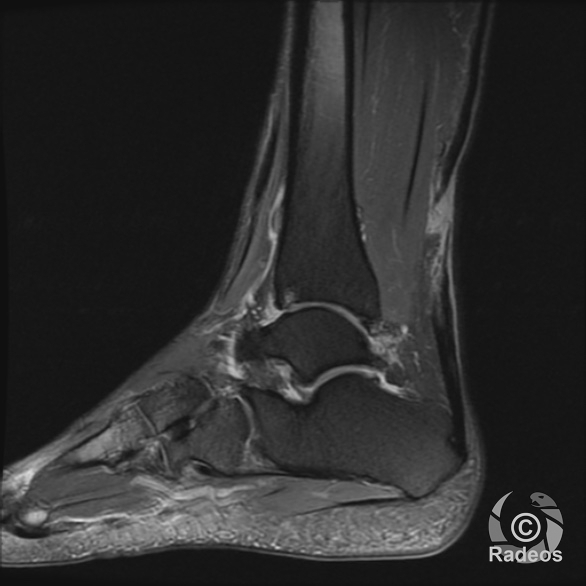

LE CAS DU MOMENT

Aspect IRM d'une fibromatose profonde de la paroi abdominale. Découverte fortuite d'un angiome hépatique gauche.